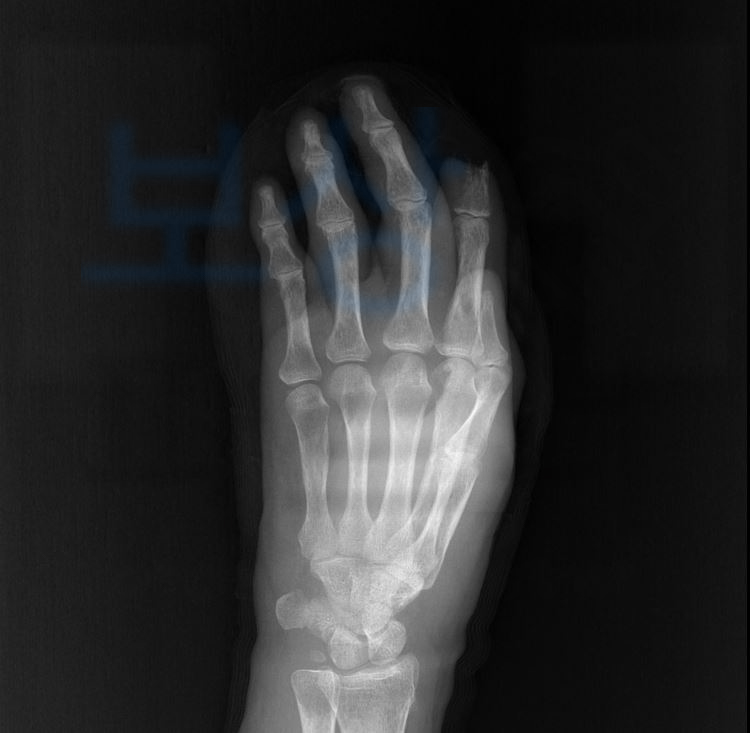

박@@님은 휴대폰을 잡고 넘어져 손가락의 뼈까지 골절되는 깊은 상처를 입고 말았습니다. 하지만 당시 겪었던 사고를 대수롭지 않게 여겼고 핀 고정술 후 고객님은 자연스레 손가락이 회복될거라고 생각하셨는데요

그런데.. 점차 나아지지 않고 점점 부어오르고 심해져가는 열감에 병원을 다시 내원해보니 손가락의 골수염 진단을 받게 되었습니다.

손가락 골수염의 진행을 막기 위해 2수지, 3수지까지 절단술을 감행하는 안타까운 사례였죠. 많은 분들이 개인적으로 처리하실 때 약관상의 내용을 보시고

후유장해 진단을 진행하였고 그 결과 의뢰인은 무려 각 손가락의 장해 뿐 아니라 손목관절의 운동범위도 제한되는 심한 장해에 해당하였고 총 55%의 지급율에 해당하였습니다.

위 장해진단서를 보시면 손목관절의 심한 장해 20% 각 손가락의 뚜렷한 or 절단 장해 35% 여기서 끝이 아니라 보험금 지급의 적정성을 증명하기 위해 손해사정서 와 증빙자료를 함께 각 보험사에 송부하였는데요,